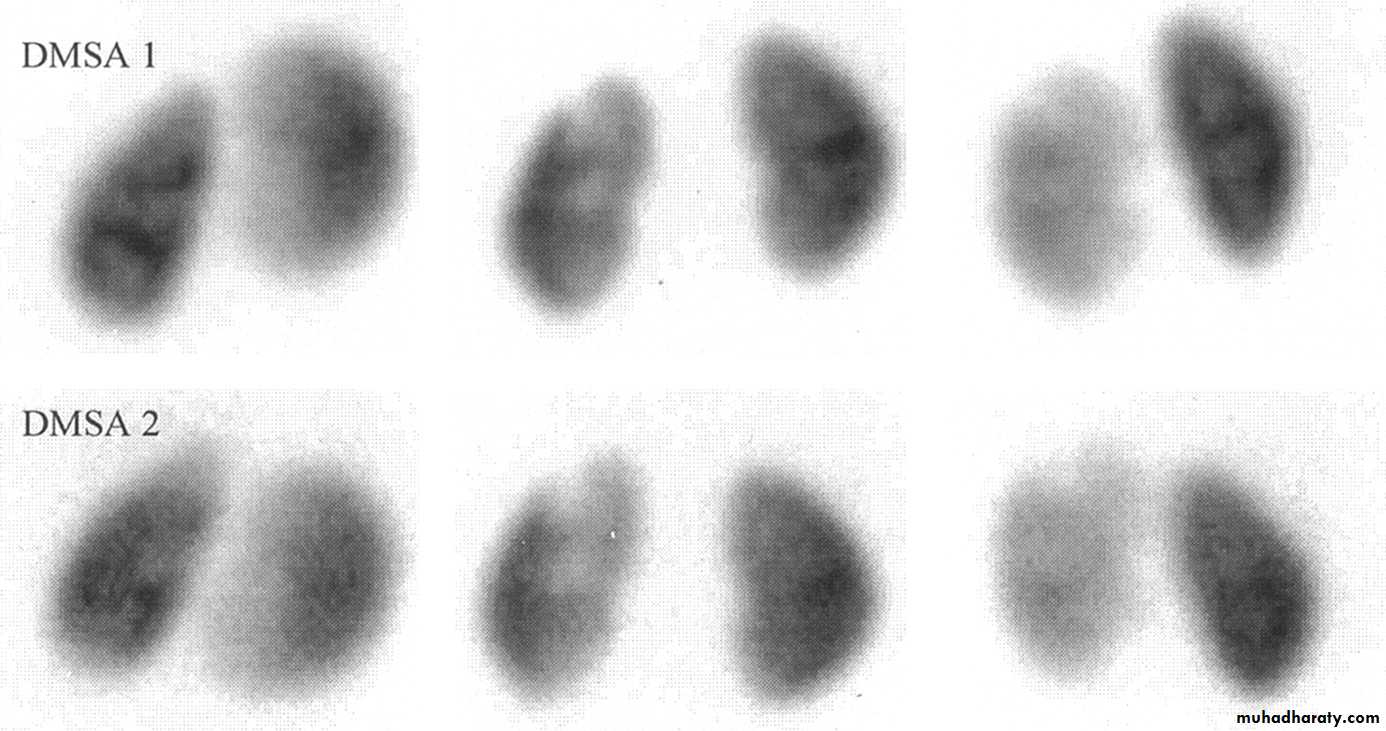

DMSA scan to detect and monitor associated renal cortical scarring.

If the patient remains asymptomatic, urine cultures are obtained periodically (e.g., every 3 months) during treatment. US and radionuclide cystogram should be obtained at yearly intervals.

Clinicians perform a dimercaptosuccinic acid scan (DMSA) to look for renal scarring at this juncture.